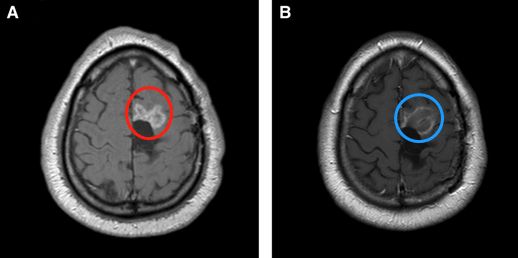

在60°C時會發(fā)生凝結(jié)性壞死引起的瞬時細(xì)胞死亡。在43°C至60°C之間的溫度下,時間和溫度的組合主要通過凋亡導(dǎo)致細(xì)胞死亡。這兩個系統(tǒng)至少部分地依賴于要消融的病變的對比光學(xué)特性以及要保留的周圍更正常的腦組織。結(jié)果,所產(chǎn)生的病變可以相對符合目標(biāo)病變的邊界。此外,這兩個LITT系統(tǒng)還利用了自然散熱器(例如相鄰的溝和水箱以及周圍的血管系統(tǒng))的優(yōu)勢,以防止熱量傳播到潛在的雄辯結(jié)構(gòu)(圖1和2)。LITT可以消融鉆孔開顱手術(shù)和傳統(tǒng)的開放式手術(shù)都難以進(jìn)入得深部病變(圖3)。由于溫度梯度迅速下降到消融區(qū)域之外,因此周圍正常的腦組織無需進(jìn)行熱消融。

圖3:51歲男性,右顳丘腦膠質(zhì)母細(xì)胞瘤術(shù)后復(fù)發(fā),LITT消融前(A)和消融后(B)顯示病灶得以毀損。